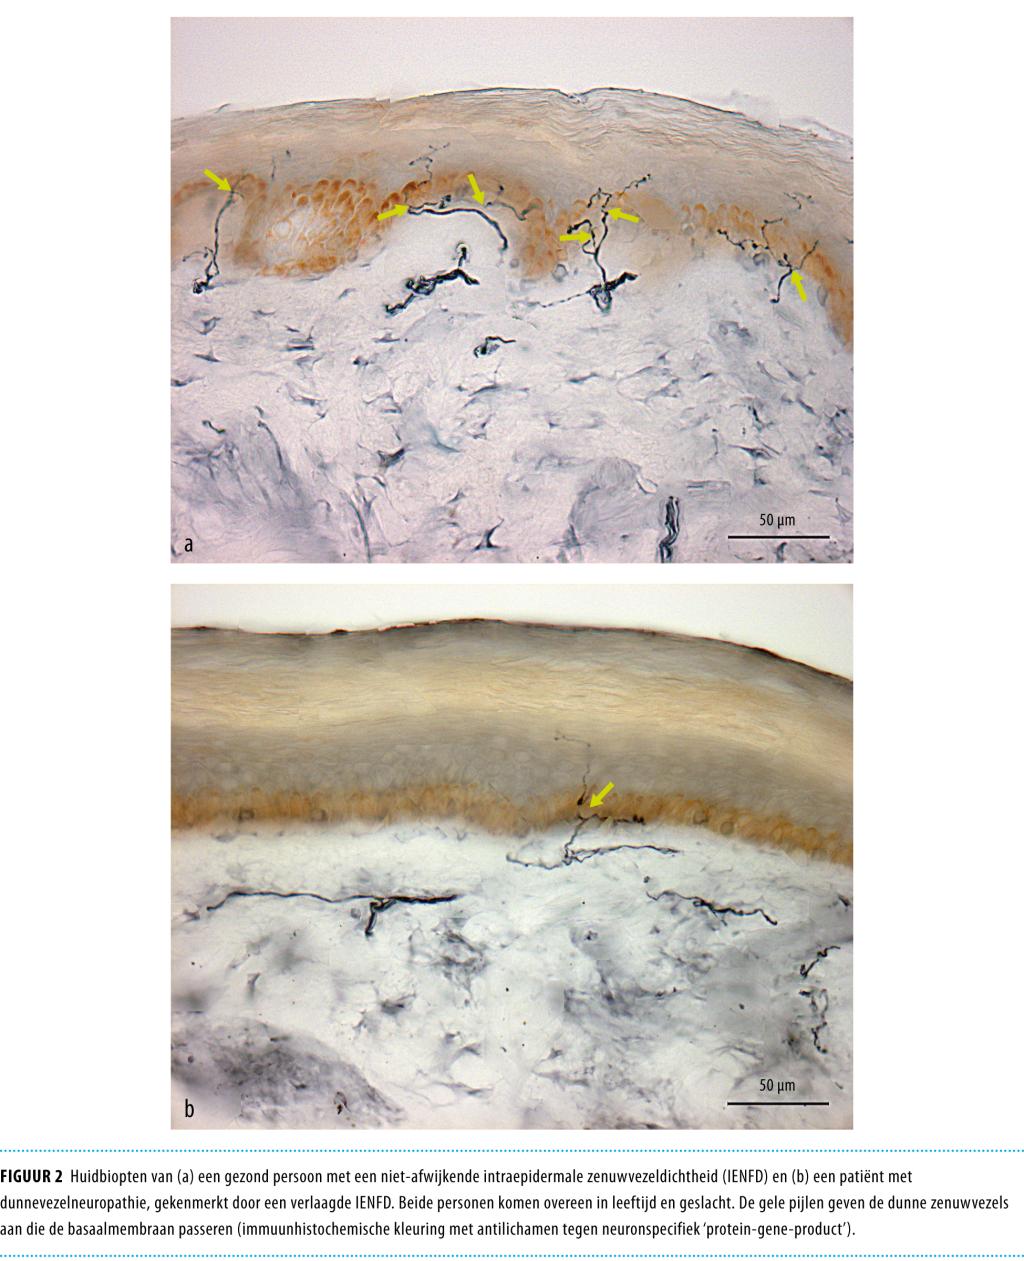

Het huidbiopt is een betrouwbare, minimaal invasieve en veilige methode voor het bepalen van de intra-epidermale zenuwvezeldichtheid (‘intraepidermal nerve fiber density’, IENFD).17 Een stansbiopt van 3 mm wordt circa 10 cm boven de laterale malleolus afgenomen, waarna het biopt een immunohistochemische kleuring ondergaat met antilichamen tegen het neuronspecifieke eiwit ‘protein-gene-product 9.5’ (PGP 9.5); vervolgens wordt het aantal dunne zenuwvezels dat de basaalmembraan passeert onder een lichtmicroscoop geteld (figuur 2).

Figuur 2